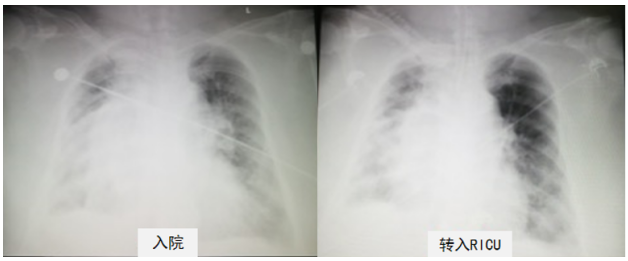

一、病情介绍 患者女性,77岁,主因“反复咳嗽、咳痰、喘息10余年,加重1月”入院。入院后出现进展性呼吸性酸中毒合并意识障碍,给予气管插管、转入RCU进一步治疗。 既往罹患高血压病,混合性睡眠呼吸暂停低通气综合征,曾于外院诊断“慢性阻塞性肺疾病”,2年前诊断右肺腺癌,正在进行靶向治疗中,脐疝,骨结核。无吸烟史,长期从事教师职业。 体温36.8℃,脉搏83次/min,呼吸18次/min,血压109/65 mmHg,插管前患者浅昏迷,插管后镇静状态,双肺呼吸音低,可闻及干啰音,腹膨隆,腹部可及直径约15 cm包块,无压痛,双下肢浮肿,BMI 43 kg/m²,重度向心性肥胖。 WBC 7.67×109/L,NEU% 76.3%,CRP 1 mg/dl,PCT 4 ng/ml。 Cre 84 μmol/L,CK 74 U/L,ALT 25 U/L,GLU 8.9 mmol/L。 MYO 62.8 ng/ml,CK-MB 5.4 ng/ml,TNI 0.0206 ng/ml,BNP 145 pg/ml,D-Dimer 2670 ng/ml。 血气分析(NIV,FiO2 0.5):pH 7.11,PaCO2 120 mmHg,PaO2 66.5 mmHg,SpO2 91%,BE 5.6 mmol/L,HCO3- 36.7 mmol/L。胸部X线片:患者心影偏大,右侧肺门偏大,双侧透亮度减低,左上肺有过度充气表现(图1)。 患者胸部X线 肥胖患者机械通气的要点和难点 (1)呼吸力学测量:临床进行呼吸治疗需要了解反映患者呼吸力学改变的指标。在对肥胖患者进行呼吸生理学指标监测时往往会发现其平台压力明显升高,我们要结合患者的影像学特点来判断平台压升高的原因,其与ARDS引起的平台压升高并不相同。向心性肥胖患者主要的病理生理变化是大量脂肪堆积,尤其是腹部脂肪堆积导致膈肌活动受限,吸气做功增加;功能残气量(FRC)明显下降,呼气动力不足;胸内压增加,引起呼气时小气道过早关闭,导致吸气和呼气双相障碍,患者呼吸做功明显增加(图3)。 图3 肥胖患者呼吸生理改变 图4 A:仰卧位自主呼吸时,由于膈肌移动受限和小气道过早关闭,导致呼吸做功增加;B:麻醉后引起呼吸肌肉功能障碍,呼吸顺应性下降,气体陷闭加重,呼吸机正压通气时背侧通气减少;C:外源性PEEP增加麻醉状态下患者背侧通气和减少气体陷闭。 (3)肺复张应用:谨慎应用,避免心输出量下降或肺容量伤。 (4)实施坐位通气:实施坐位通气改善患者肺内分流。对于肥胖患者,坐位通气是可行的。坐位情况下,患者腹部活动空间更大,胸腔内压力会降低。 (5)自主呼吸试验(SBT):文献显示,低水平PS和CPAP可能低估肥胖患者拔管后的呼吸做功,因此建议设置PS为0,PEEP为0,以提高SBT的准确性。但这种方法似乎比T管呼吸做功更高,SBT成功难度更大,因此在PS和PEEP为0的情况下,如果患者能够通过SBT,其拔管成功率可能会更高。 患者的评估是呼吸治疗的第一步,包括基础状态评估(包括意识、镇静镇痛、肌力)、营养状态评估、呼吸力学评估、血流动力学评估、膈肌功能评估。 基础状态评估:GCS评分E3+VT+M5;RASS评分+1~+2分;BPS疼痛程度评分3分;MMT评估双上肢肌力Ⅳ级,双下肢肌力Ⅲ级;四肢肌张力正常;插管前存在谵妄状态;长期卧床。 营养风险筛查(NRS)评分6分,属于营养不良高风险人群。 呼吸系统评分:胸廓正常;右肺湿啰音,双下肺呼吸音低;痰液较多,黄色,黏稠;咳嗽能力弱;胸片示双肺斑片影,双侧胸腔少量积液;经口气管插管, 容控模式,Vt 360ml,RR 16次/min, PEEP 8 cmH2O,FiO2 0.6,Flow 55 L/min。呼吸力学评估:①呼吸机肺功能监测:Ppeak 55 cmH2O,Pmean 18.9 cmH2O,总PEEP 8 cmH2O,PEEPi 6 cmH2O,Pplat 32 cmH2O,Vt 360 ml,RR 20次/min, FiO2 0.8。②气道阻力(R):23 cmH2O/(L·s)[正常值:<10 cmH2O/(L·s)];③肺顺应性(C):15 ml/cmH2O(正常值:50~100 ml/cmH2O)。 三、呼吸治疗策略及需要关注的问题 四、撤机困难与呼吸康复 困难撤机病因与相关因素分析 表1 常见影响患者撤机的病生理因素临床分析表 安全评估:①呼吸系统;②循环系统;③神经系统。 基础状态:意识、疼痛及躁动程度;肌力、肌张力评估;谵妄及吞咽能力评估。 营养风险:近1个月体重下降>5%;近1周营养摄入>总量60%。 一阶段目标:①恢复自主呼吸;②使患者处于45°坐位,改善肺内分流,提高肺泡通气。 二阶段目标:①促进痰液引流;②提高四肢肌力;③改善耐力与活动能力;④早期拔管,序贯无创通气;⑤患者恢复自理能力,脱离重症单元。 五、小结 参考文献 [1] Kacmarek R M, Wanderley H V, Villar J, et al. Weaning patients with obesity from ventilatory support[J]. Curr Opin Crit Care, 2021, 27(3):311-319. [2] Grassi L, Kacmarek R, Berra L. Ventilatory Mechanics in the Patient with Obesity[J]. Anesthesiology, 2020, 132(5):1246-1256. [3] De Jong A, Wrigge H, Hedenstierna G, et al. How to ventilate obese patients in the ICU[J]. Intensive Care Med, 2020, 46(12):2423-2435. 作者简介 钟雪锋 北京医院呼吸与危重症医学科 副主任医师 北京市医学会呼吸病学分会危重症学组委员 中国老年学和老年医学学会呼吸与危重症分会委员 长期在呼吸重症监护室工作,擅长机械通气、复杂感染、肺间质疾病急性进展等 参与国家级课题研究多项,发表论文20余篇 声明: